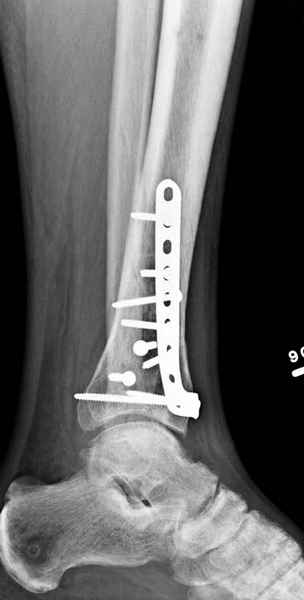

Публикации за последние пять лет показывают, что в лечении переломов пилона важным является состояние

мягких тканей. Поэтому при лечении пилона, особенно после высокоэнергетической травмы, необходимо придерживаться правила - лучше проводить запоздалую фиксацию, чем после операции иметь проблемы с мягкоткаными осложнениями.

Закрытый метод фиксации рекомендуется, когда фрагменты были сопоставлены в результате лигаментотаксиса, а открытый минимальный метод при нерепонированных отломках.

После репозиции сустава необходимо удостовериться

в заполнении образовавшейся полости ауто- или синтетическими заполнителями, что в последующем предохраняет от варусного коллапса.

После ExFix проведение компьютерной томографии считаем обязательным, получаем информацию о расположении крупных фрагментов, которая подскажет сторону операционного доступа и направления проведения фиксирующего материала.

Фиксация наружной лодыжки подсказывается переломом, а малоберцовая является ключом-ориентиром для длины конечности.

Любая фиксация - преконтурированные пластины с уголовой стабильностью, медиальная, латеральная в зависимости от нахождения отломков или наружная фиксация типа аппарата Илизарова подходят для ранней мобилизации.

Не все переломы пилона фиксируются медиальной

пластиной, поэтому, учитывая что большой фрагмент

находится на латеральной стороне, я бы применил

передне-латеральную пластину.